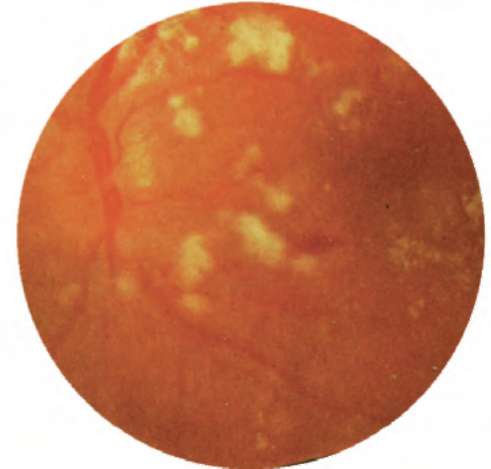

Рис. 20.2. Глазное дно при злокачественной артериальной гипертонии. Резкий спазм артерий, вены расширены. Многочисленные ватообразные и точечные очаги, кровоизлияния, неравномерность пигментации и отек сетчатки